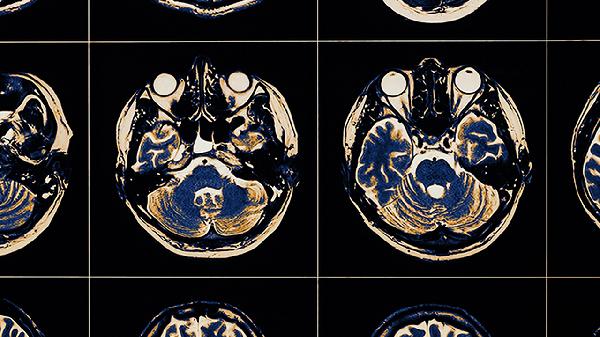

脑病的治疗方法

脑病的治疗方法主要有生活干预、物理治疗、药物治疗、手术治疗等方式。脑病可能与遗传、感染、外伤、代谢异常、脑血管病变等因素有关,通常表现为头痛、意识障碍、运动功能障碍等症状。